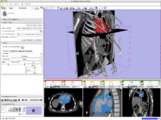

B-Spline Registration in Slicer 3.6 allows for non-rigid registration between pre-procedure MRI and intra-procedure CT images during CT guided tumor ablation in the liver. It provides increased tumor visualization during the planning, targeting and monitoring phases of the ablation procedure.